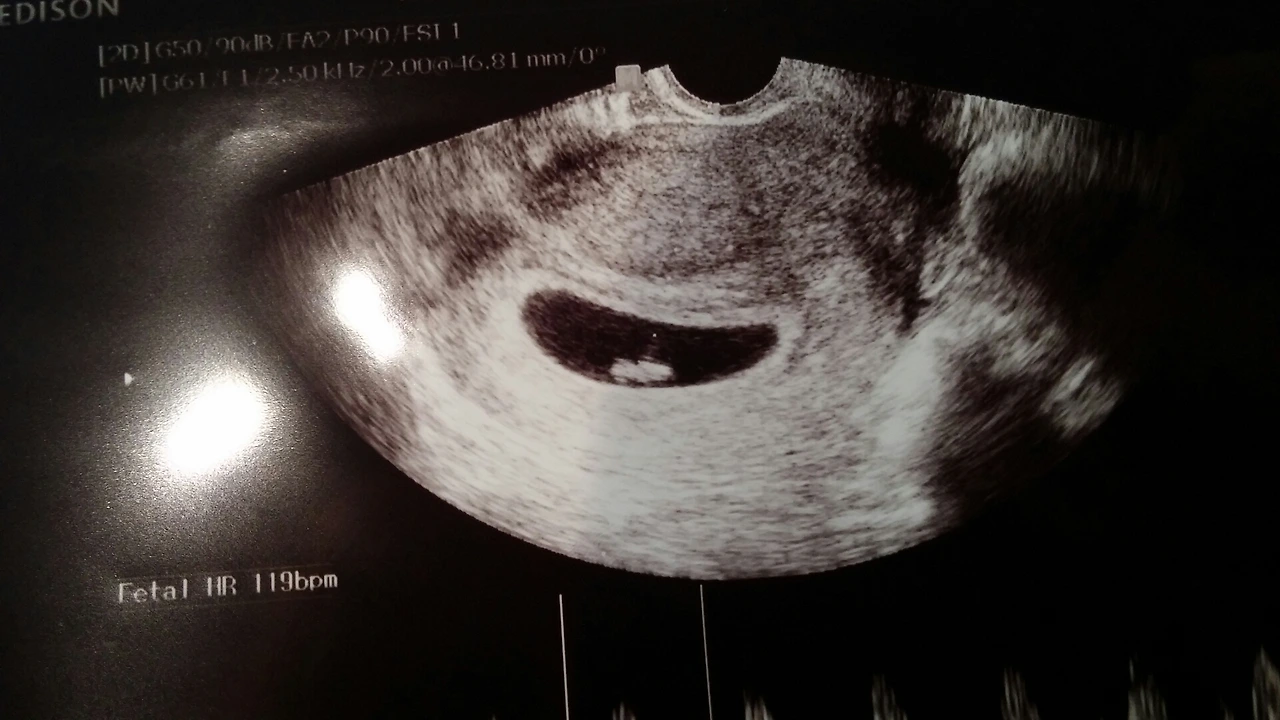

설렘과 두려움의 묘한 대기시간이 지나고 여자의 이름이 호명되었다. 간단한 질의를 끝낸 쌤이 초음파를 보겠다며 민망하고 요상한 의자에 앉으라고 했다. 아기를 낳을 때 까지도 익숙해지지 않던 그 의자에 앉아 초조한 시간이 흐른 후 쌤은 여자에게 임신을 확인과 함께 축하의 인사를 전해주었다. 간호사님은 급히 남자를 불러왔다.

남자가 진료실에 들어오자 여자는 눈물이 날 것 같았다. 대부분 테스트기를 확인한 예비산모들은 4주 혹은 그 전에 산부인과에 방문하게 되어 첫 방문에는 아기의 심장소리를 들을 수 없다. 그러나 미련 곰탱이 같은 여자의 콩알만 한 아기는 벌써 7주! 첫 방문과 함께 아기의 심장소리도 듣게 된다.

쿵 쿵 쿵 쿵 쿵 쿵...

규칙적인 비트로 빠르게 쿵쿵하던 콩알만 한 녀석의 심장소리.

신기하고 꿈만 같던 그 찰나의 순간!!

묘한 감정에 휩싸인 여자와 남자의 눈에 눈물이 고였다.